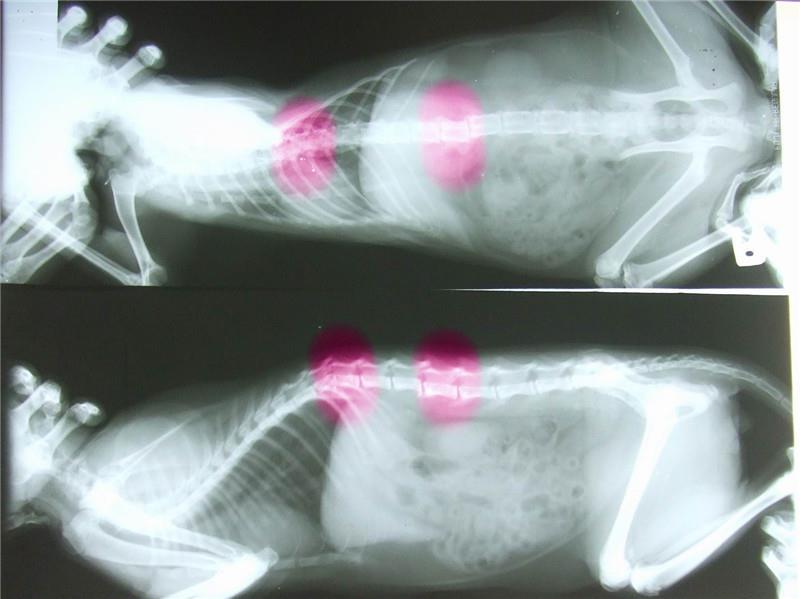

拍了X 光片看來, 醫師說二個關節出錯, 一個錯位 ,一個骨折,身上的傷口對稱,醫師研判被狗咬 , 嚴重傷到神經後二腳無法行走 , 癱瘓

經過一小段時間後二腳做針糾有反應 , 會行走,但突然病情惡化需要上點滴維持生命, 沒幾天牠就走了,希望大家幫幫牠的醫療費